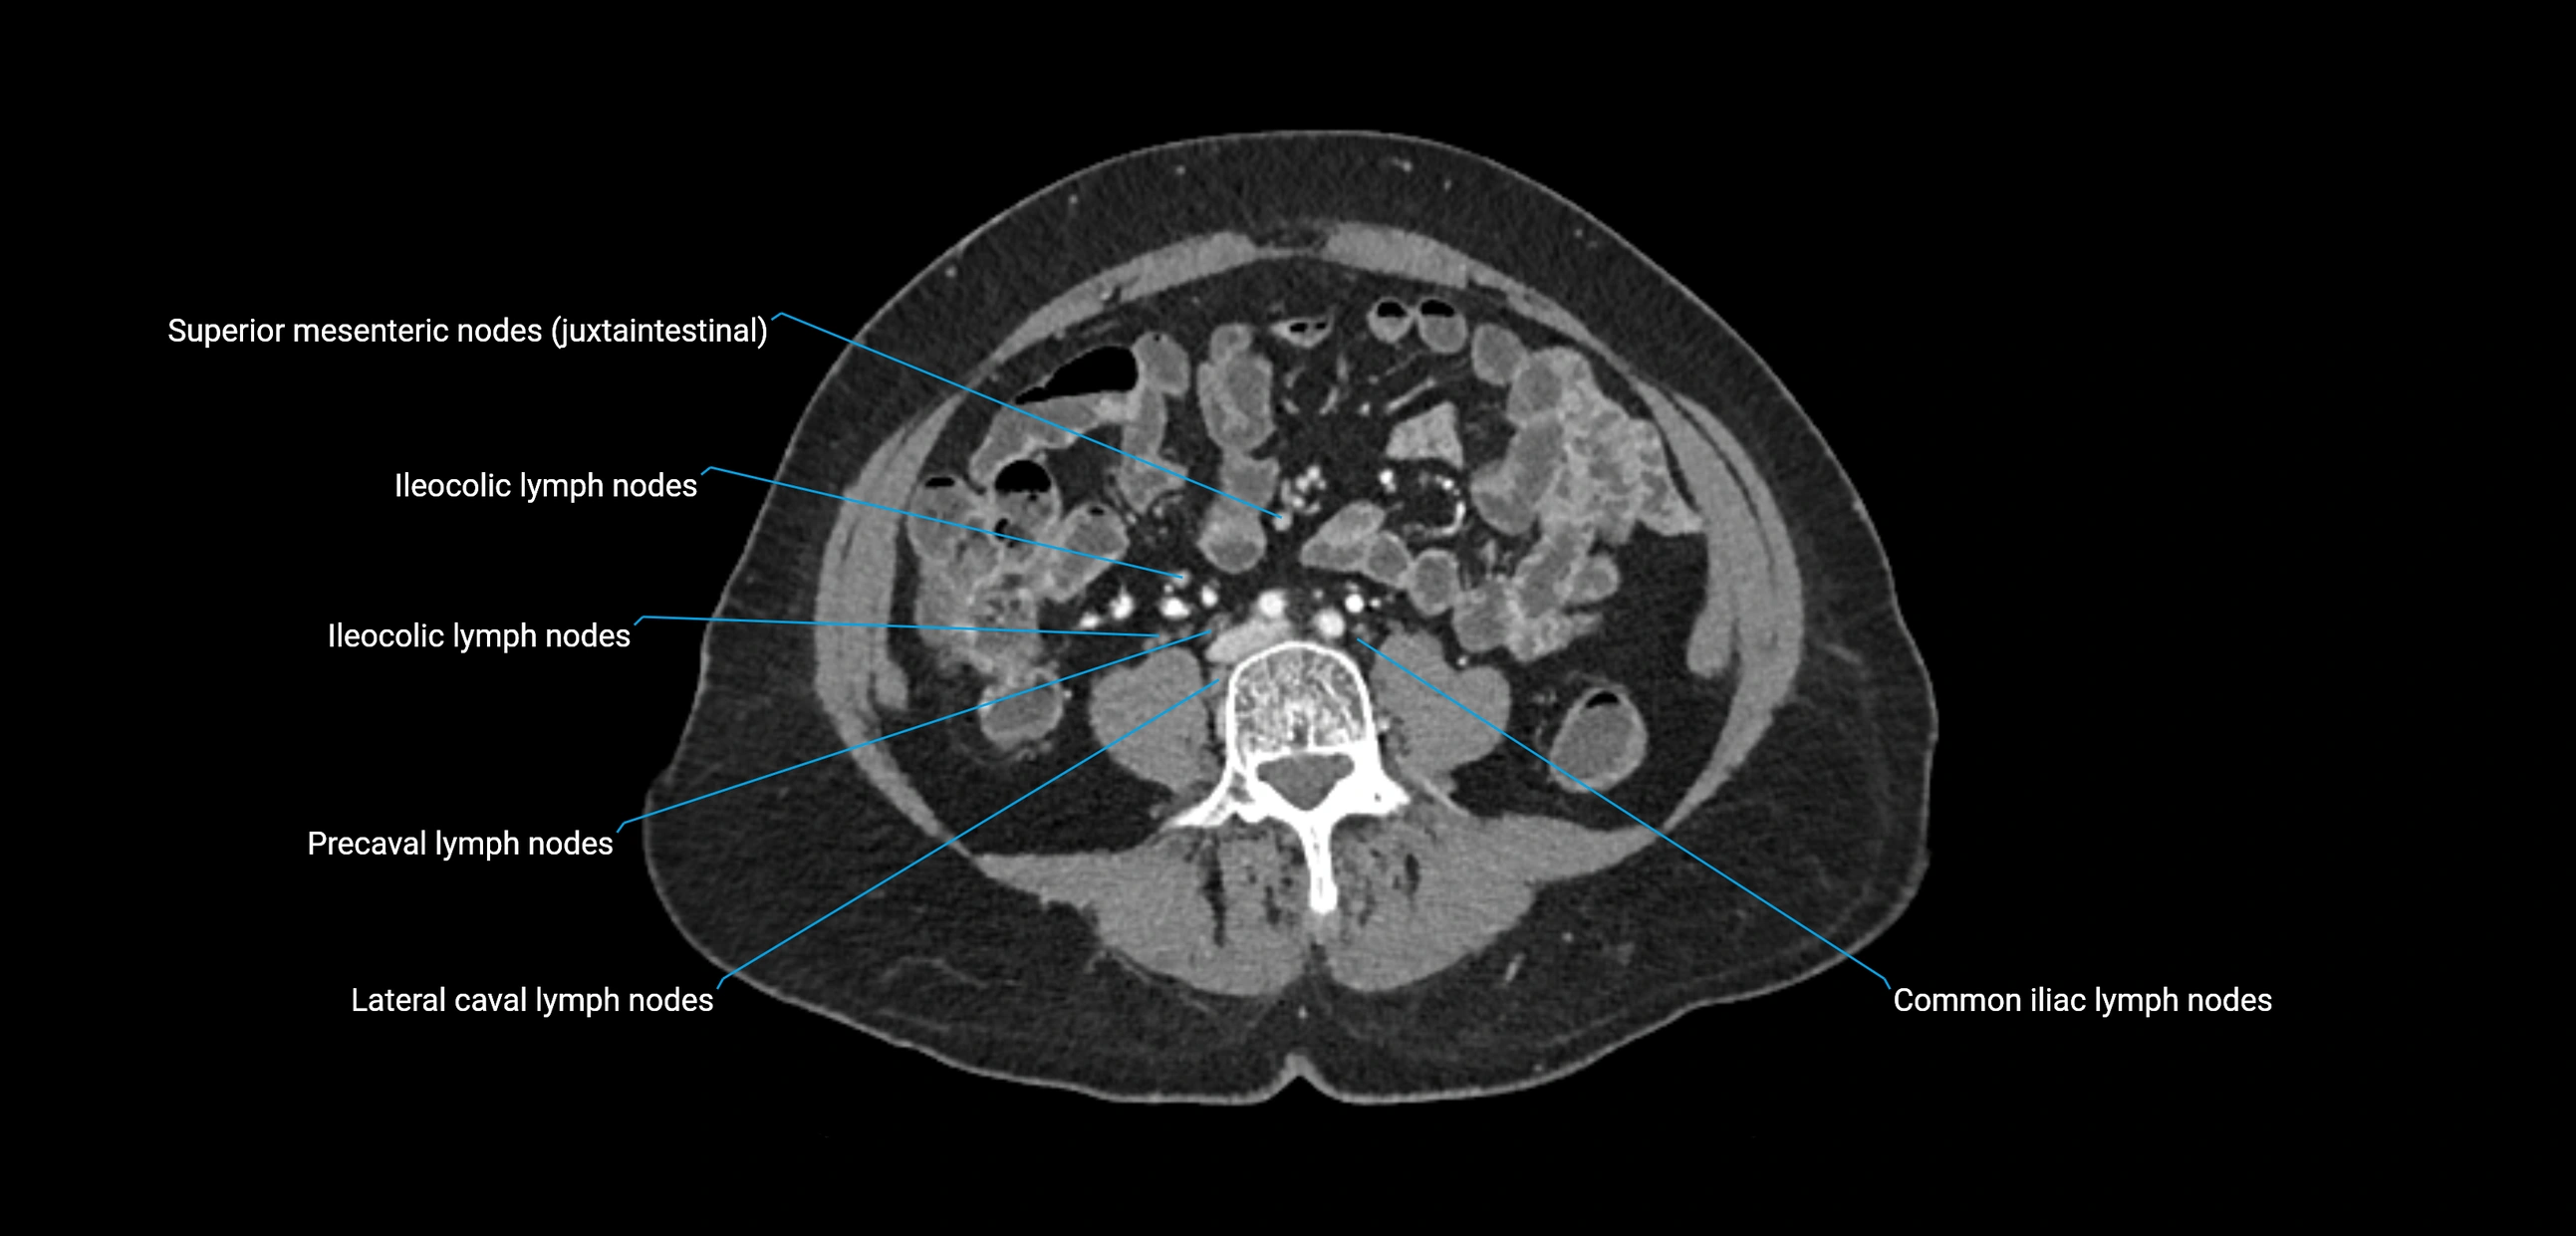

CT image

image